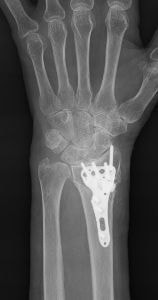

尺骨突き上げ症候群

遠位橈尺関節の不安定性を伴う尺骨突き上げ症候群に対する尺骨短縮術の術前(左)と術後(右)。術後には関節の不安定性が消失し、疼痛も出現しなくなった。

前腕にある2本の骨:橈骨(とうこつ)と尺骨(しゃっこつ)の長さが有意に異なることによって起こる障害の一つです。尺骨突き上げ症候群は、尺骨が橈骨よりも長いことによって起こる手関節尺側部の障害の総称です。尺骨が橈骨より長いこと自体は悪いことではありませんが、長年の使用により疼痛を生じる原因となる場合があります。尺骨が長くなる原因のほとんどは先天的な素因によるものですが、橈骨の骨折によって生じることもあります。

症状は、手の使用に伴う手関節尺側部の疼痛ですが、疼痛の原因は、尺骨の突き上げによる三角線維軟骨(関節円板)の損傷、手根骨の挫傷、橈尺靱帯の損傷のほか、橈尺関節の不適合による関節症変化など様々であり、これが”症候群”と呼ばれる所以です。

治療は、症状の原因に対してピンポイントに行うことが原則ですが、尺骨突き上げ症候群においては『どの要素が最も症状に関与しているか?』を見極めることが困難であるため、相当期間の安静を保っても症状が改善しない場合には、すべての要素を同時に治療すべく『尺骨短縮(骨切り)術』を行います。

具体的には、前腕尺側の皮膚切開から尺骨を骨切して短縮し、プレートとスクリューを用いて固定します。しっかりと固定されれば早期から簡単な手の使用は可能ですが、手関節に負荷が掛かる動作・業務・スポーツは、3ヶ月ほど控えていただく必要があります。